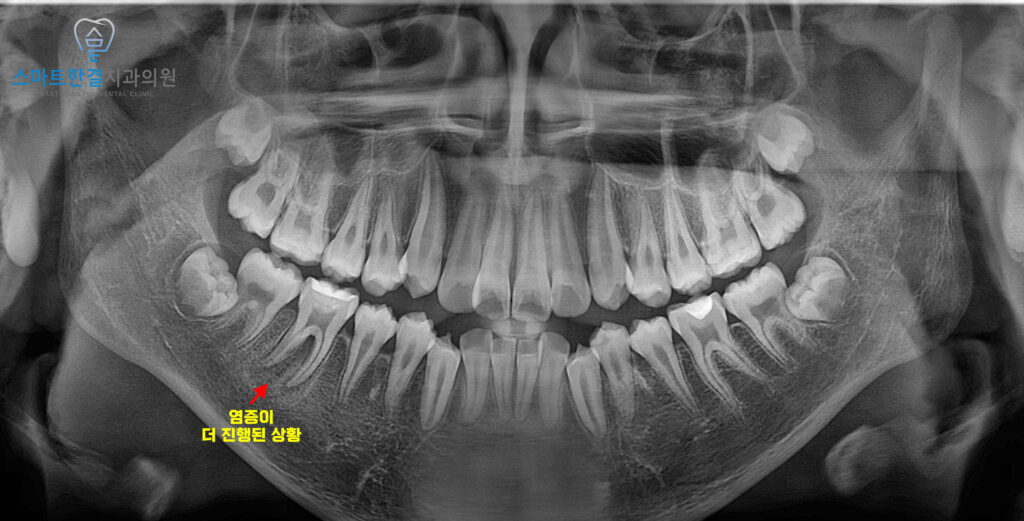

치료 이후 5개월 뒤,

환자분께서 다시 내원하셔서

잇몸 부기가 재발한 것 같다고

말씀하셨어요.

이를 확인하기 위해

정밀 검사를 진행한 결과,

치근분지부 쪽으로 방사선 투과상이

더 진행된 것을 확인할 수 있었는데요.

즉, 염증이 여전히 치아와

주변 조직으로 확산되어 있었고,

추가적인 치료가 필요한 상태였어요.